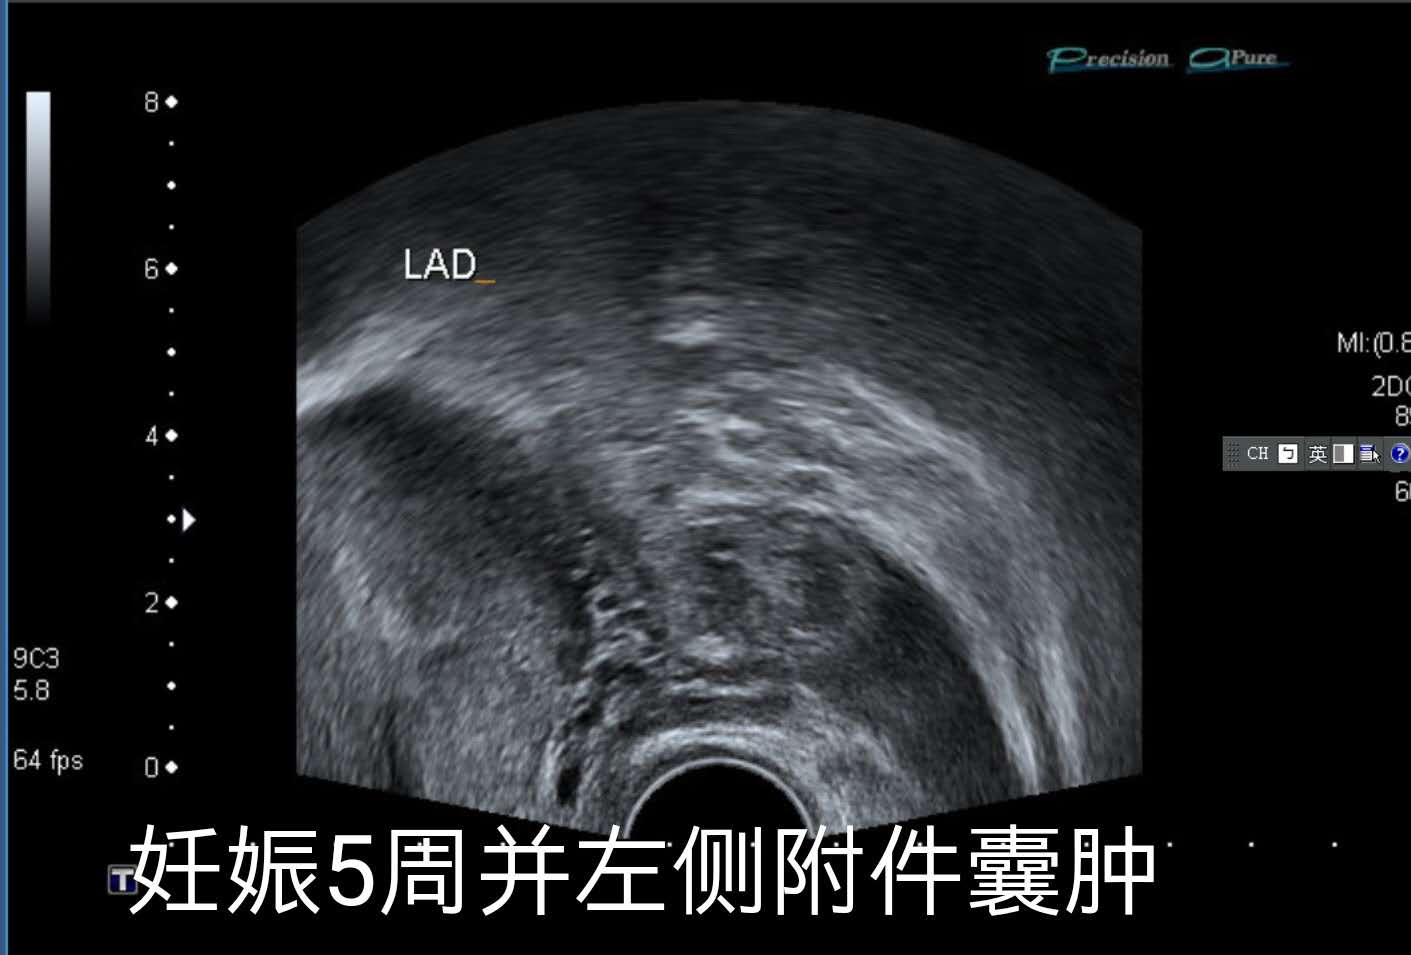

2019年3月5日的B超。

2019年3月5日,小兰再次来到佛教医院复查,医生给她查了阴道B超检查,确认了她怀有宫内活胎。

同时,医生还发现了小兰的左侧附件有个囊肿。由于小兰两年前就有左侧附件的崎胎瘤,目前小兰也没有什么特别不舒服,因此,医生没有对小兰做特别的处理。